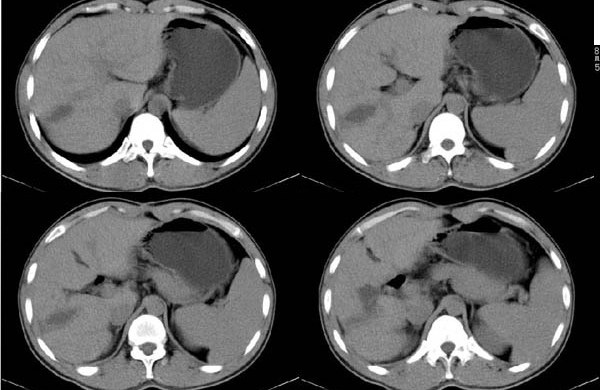

标题: CT4408:(续)肝癌术后CT表现

肝癌术后3个月(该患者硕士研究生,在四川开了一个宾馆.于做ct后第三天便在四军大西京医院做了手术,手术顺利.病人恢复良好.病理结果:肝细胞癌.最后诊断:原发性肝癌.)

10mm层厚扫描:

要注意随访哦。